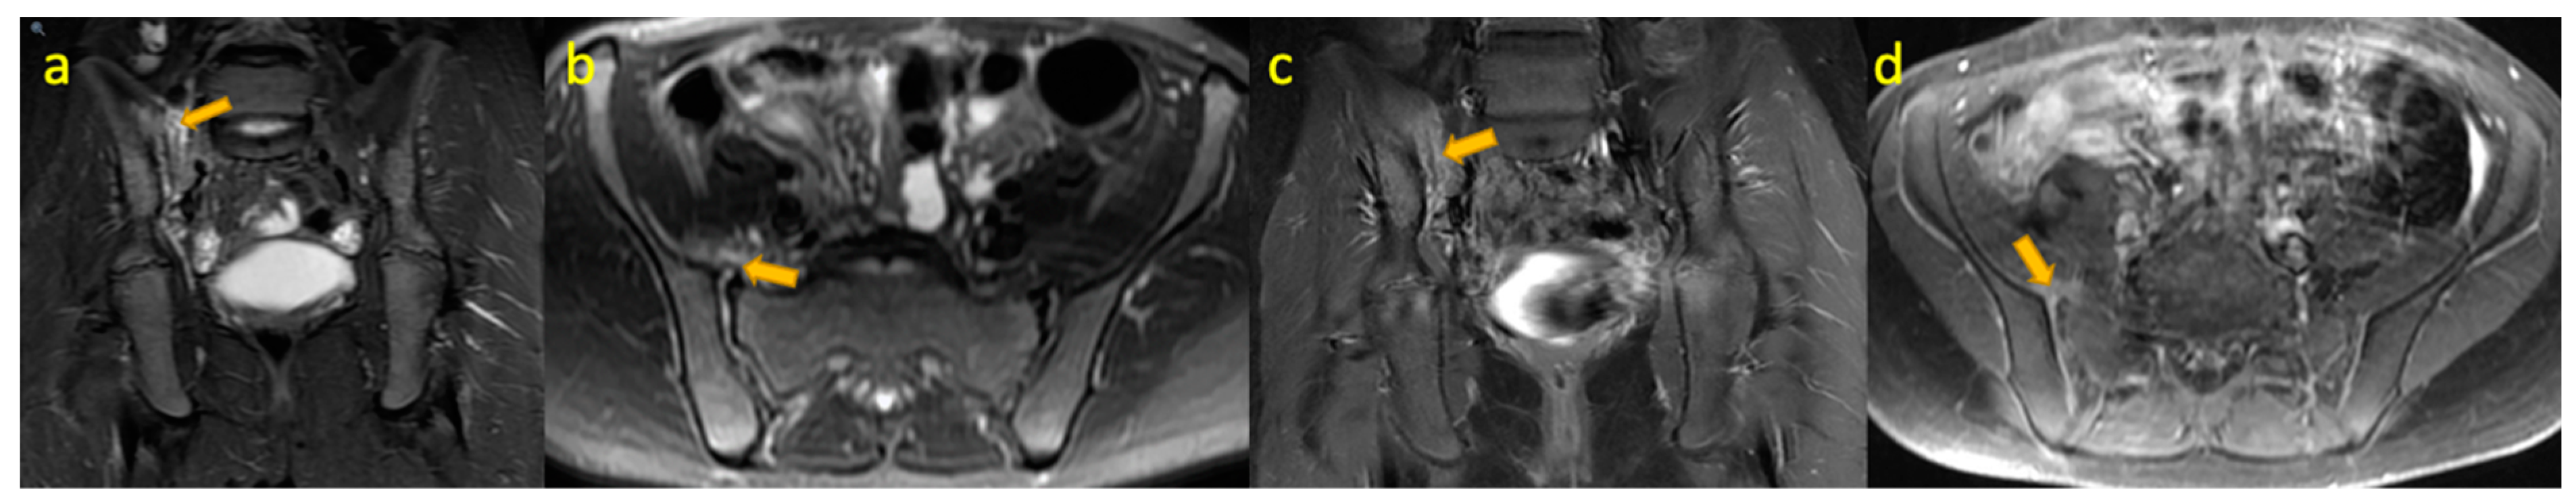

13. Septic Arthritis of the Sacroiliac Joint